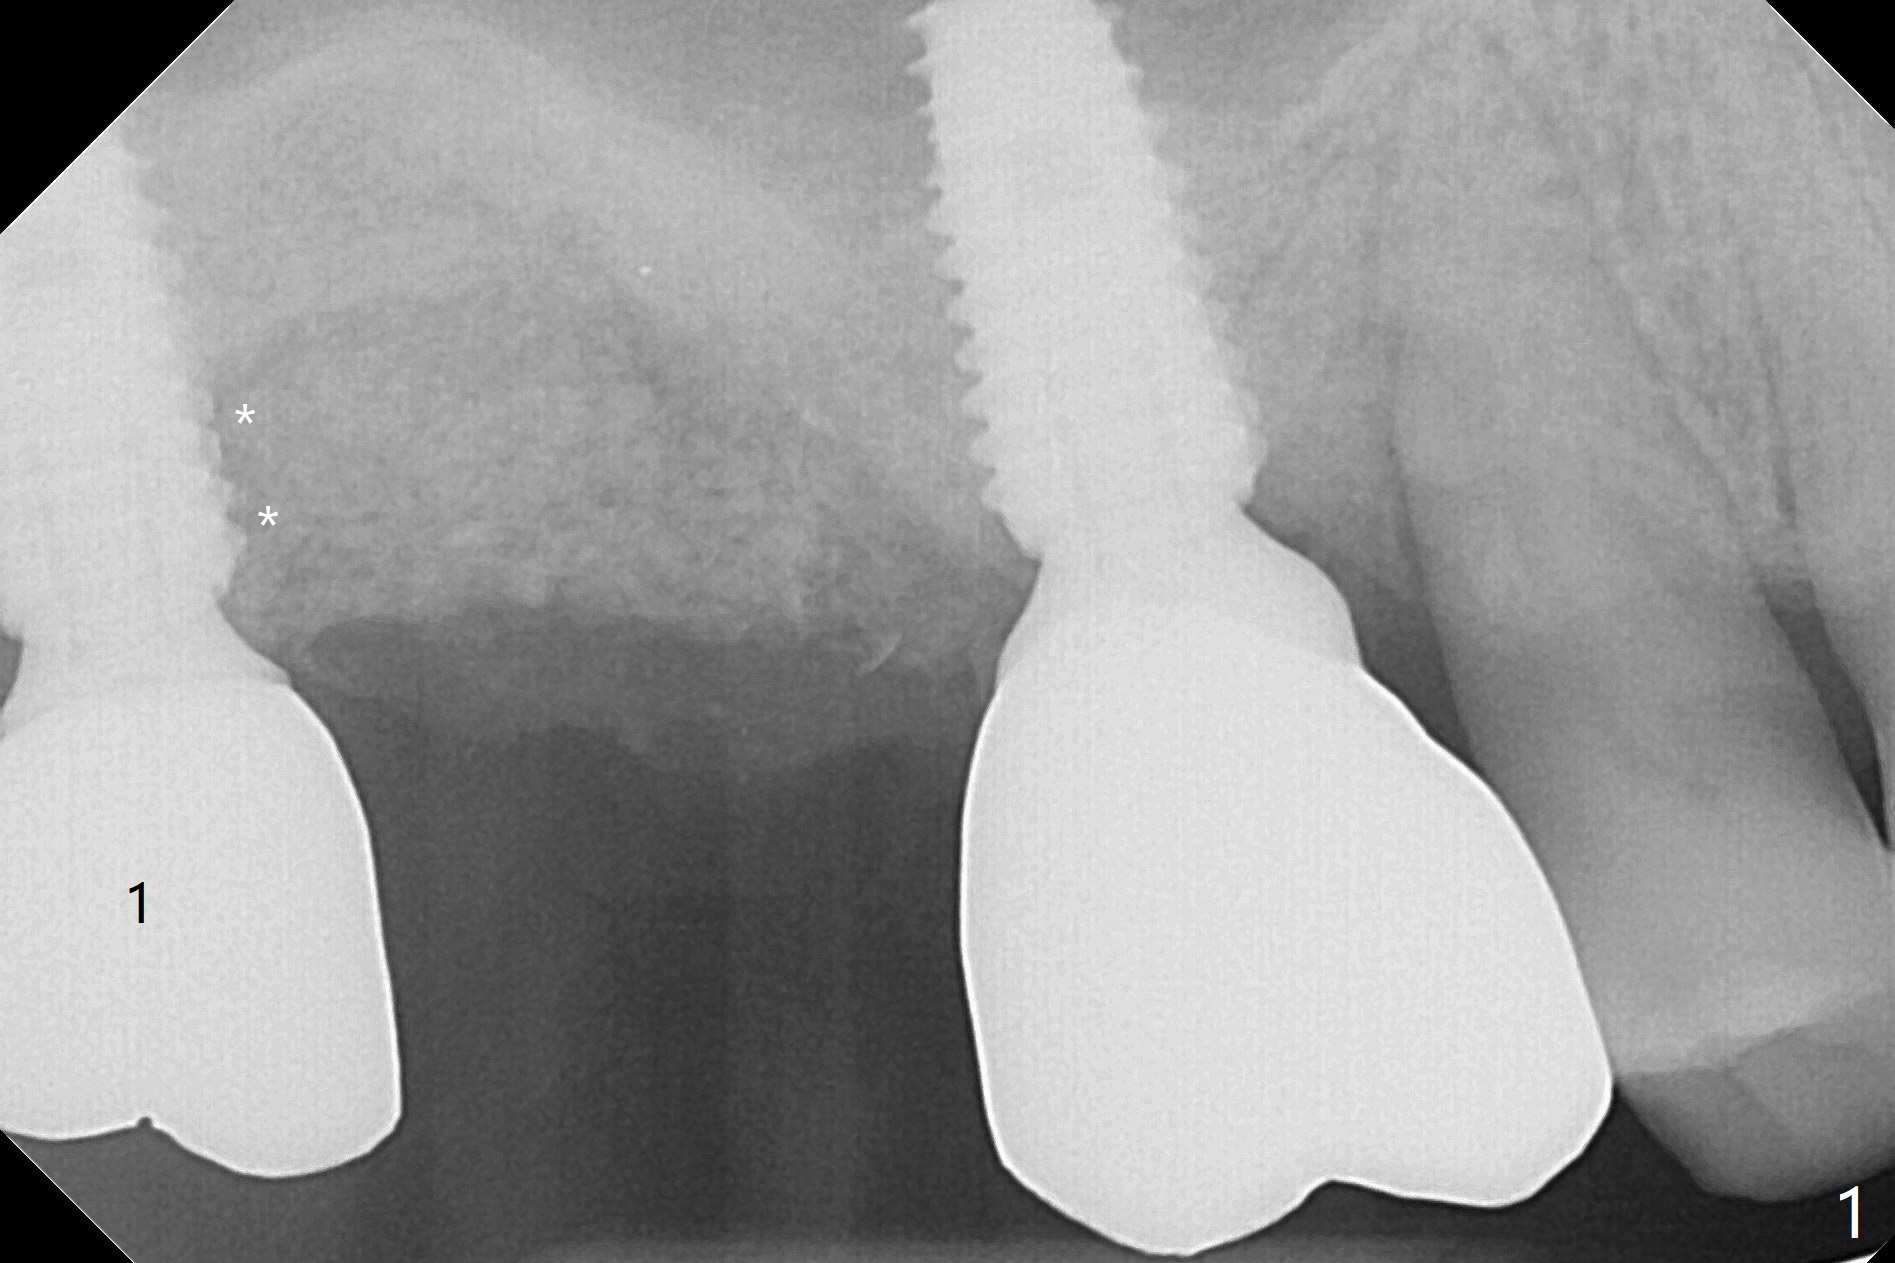

Removal of the implant at #2 is extremely difficult because of fusion of the abutment with the implant.  Buccal and palatal incisions are made to remove the bone buccomesiodistal to the implant.  After implant removal, the exposed mesial coronal implant threads at #1 are cleaned with Titanium brush; allograft is placed against the exposed threads (Fig.1 *), followed by 2 pieces of PRF membrane and 6-month collagen membrane.  Periodontal dressing is applied after suturing.  Partially due to traumatic implant removal and partially due to easy and repeated loss of periodontal dressing, bone height reduces nearly 4 months postop (compare Fig.2,3).  More discouraging is the invasion of loose nonkeratinized buccal gingiva into the healed socket nearly 4 months post graft (Fig.4 N).  Tissue punch thorough a guide should expose the implant site to the nonkeratinized tissue.  Can we fabricate a guide with buccal clearance underneath so that a flap can be raised buccally, i.e., to push the palatal keratinized tissue buccally?